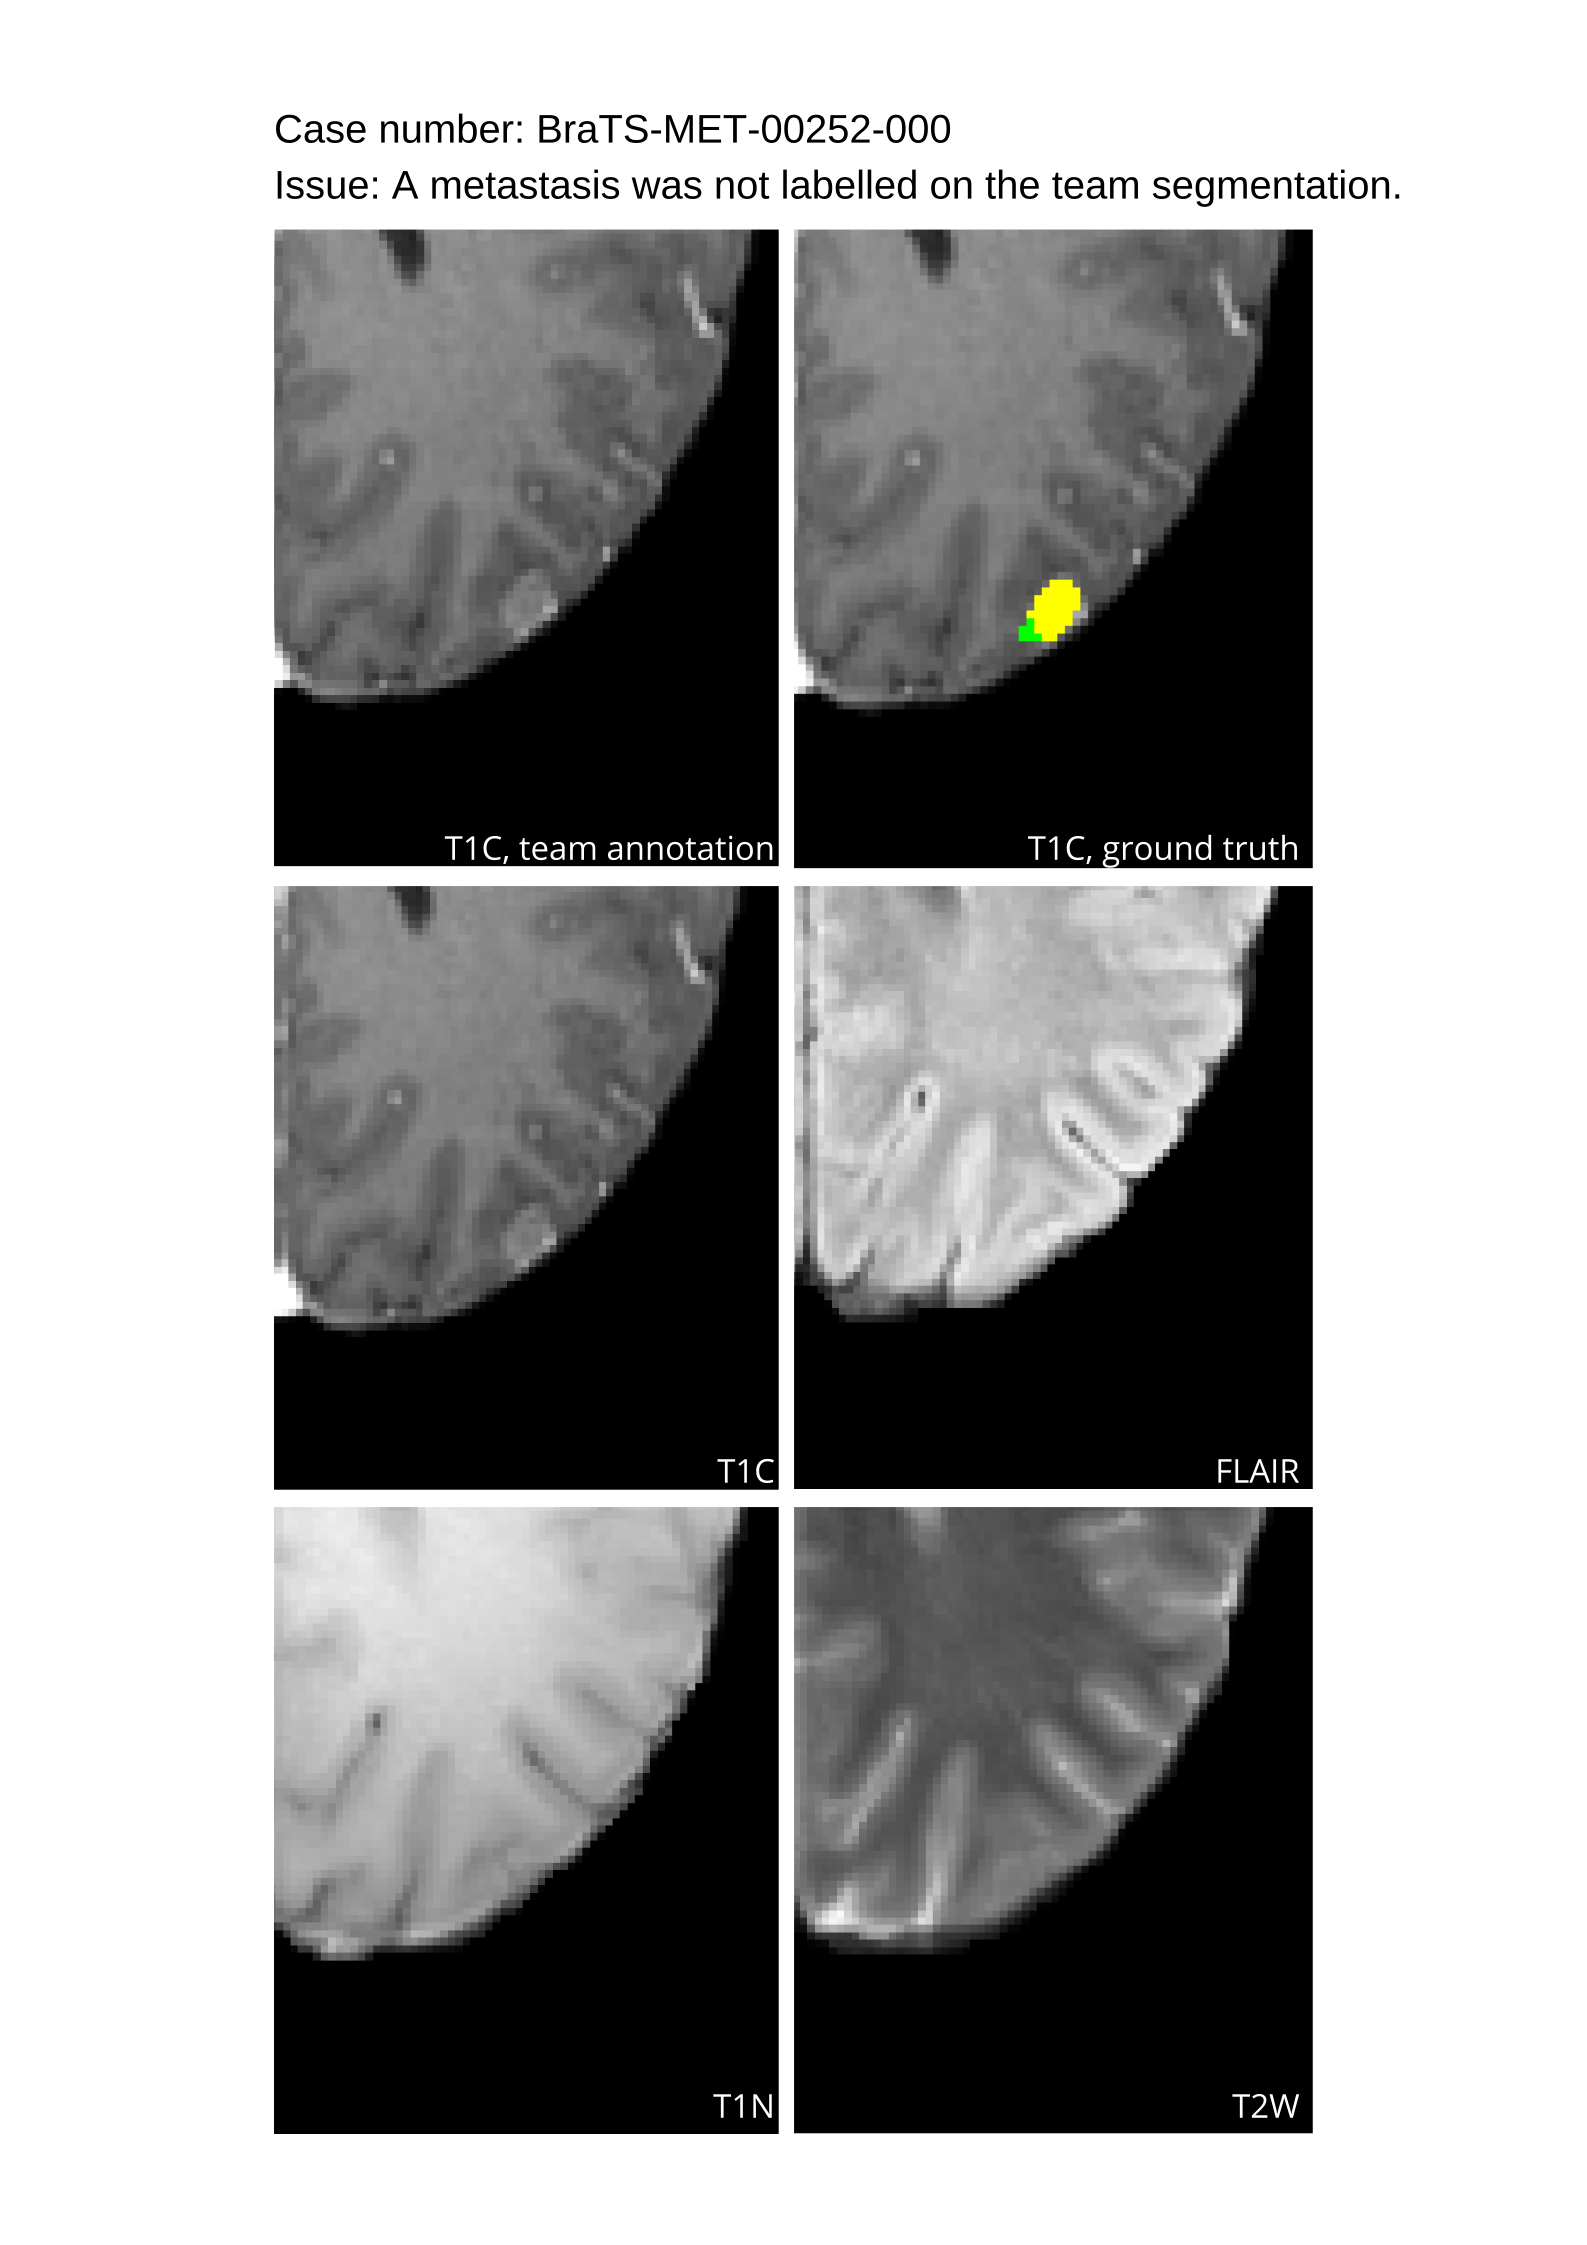

Automated algorithms missing small metastases. Enhancing metastasis was fused using the minority voting algorithm to aggregate all enhancing tumor voxels identified by the three algorithms. However, many small metastases were missed and were manually segmented by neuroradiology attendings.

Acknowledging the variability in lesion significance arising due to human error, a volumetric threshold of 2 voxels (2 mm3superscriptmm3\text{mm}^{3}mm start_POSTSUPERSCRIPT 3 end_POSTSUPERSCRIPT) was established by an expert panel of clinical radiologists, below which the models’ performance on deemed ”small/false” lesions is not considered in the evaluation. This approach was primarily adopted to ensure that participants were not unfairly penalized for stray voxels in the GT labels, which may result from human error, or for small lesions unrelated to the pathology central to the challenge. The expert panel of clinical radiologists also determined the dilation factor, which was uniformly applied for combining lesions in the GT masks. A dilation factor of 1 voxel in 3D space was chosen because BMs can be small, and it is important to avoid combining these small BMs.

Table 4 provides the relative ranking for each team. Team NVAUTO ranked first in the challenge, with an average rank across subjects of 7.9 and a PatientWise mean of 0.38. Team SY placed second with a PatientWise mean of 0.41 across all patients. The supplementary material depicts the pitfall cases with figures illustrating the false positives or missed lesions.